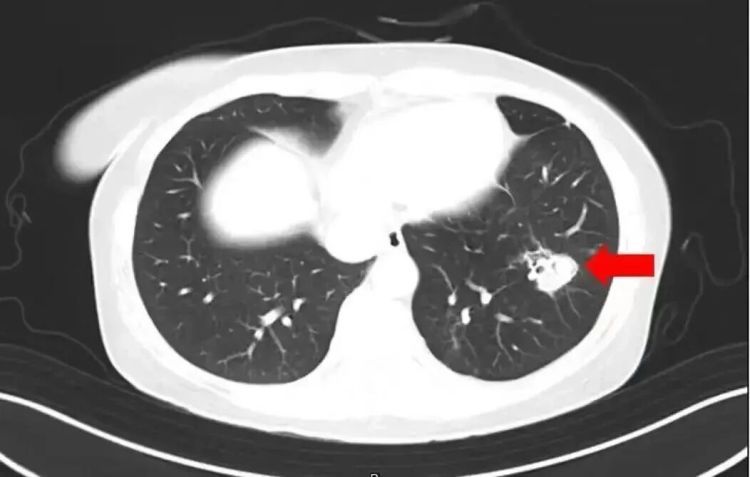

6岁女孩发烧17天

脑子被“啃”出十几个洞

近日,一6岁女童因持续发烧17天且意识不清,被转至郑州郑大一附院治疗。医生检查后大吃一惊:孩子脑子竟被“啃”出大大小小十几个洞,再晚来几天可能会被“啃空”。抽取洞内积液检测后,医生锁定了“真凶”——烟曲霉菌。

医生介绍,烟曲霉菌常隐藏在潮湿环境中,孩子在此玩耍后,霉菌通过呼吸道进入血液系统,进而“爬”进了脑子。